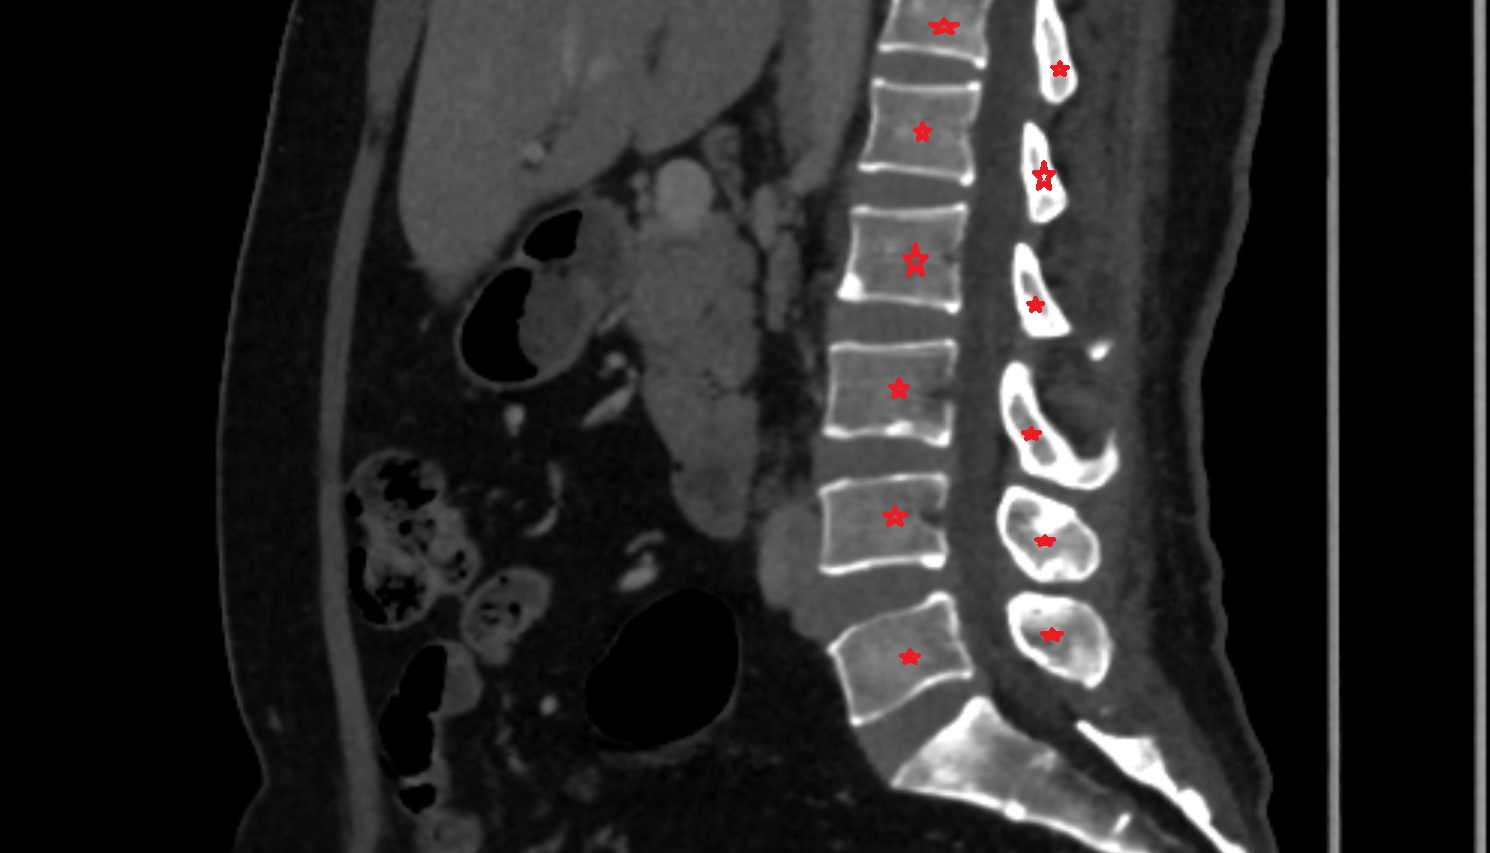

- L4–L5 Intervertebral Disc

- L3–L4 Intervertebral Disc

- L2–L3 Intervertebral Disc

- L1–L2 Intervertebral Disc

- T12–L1 Intervertebral Disc

- Vertebrae